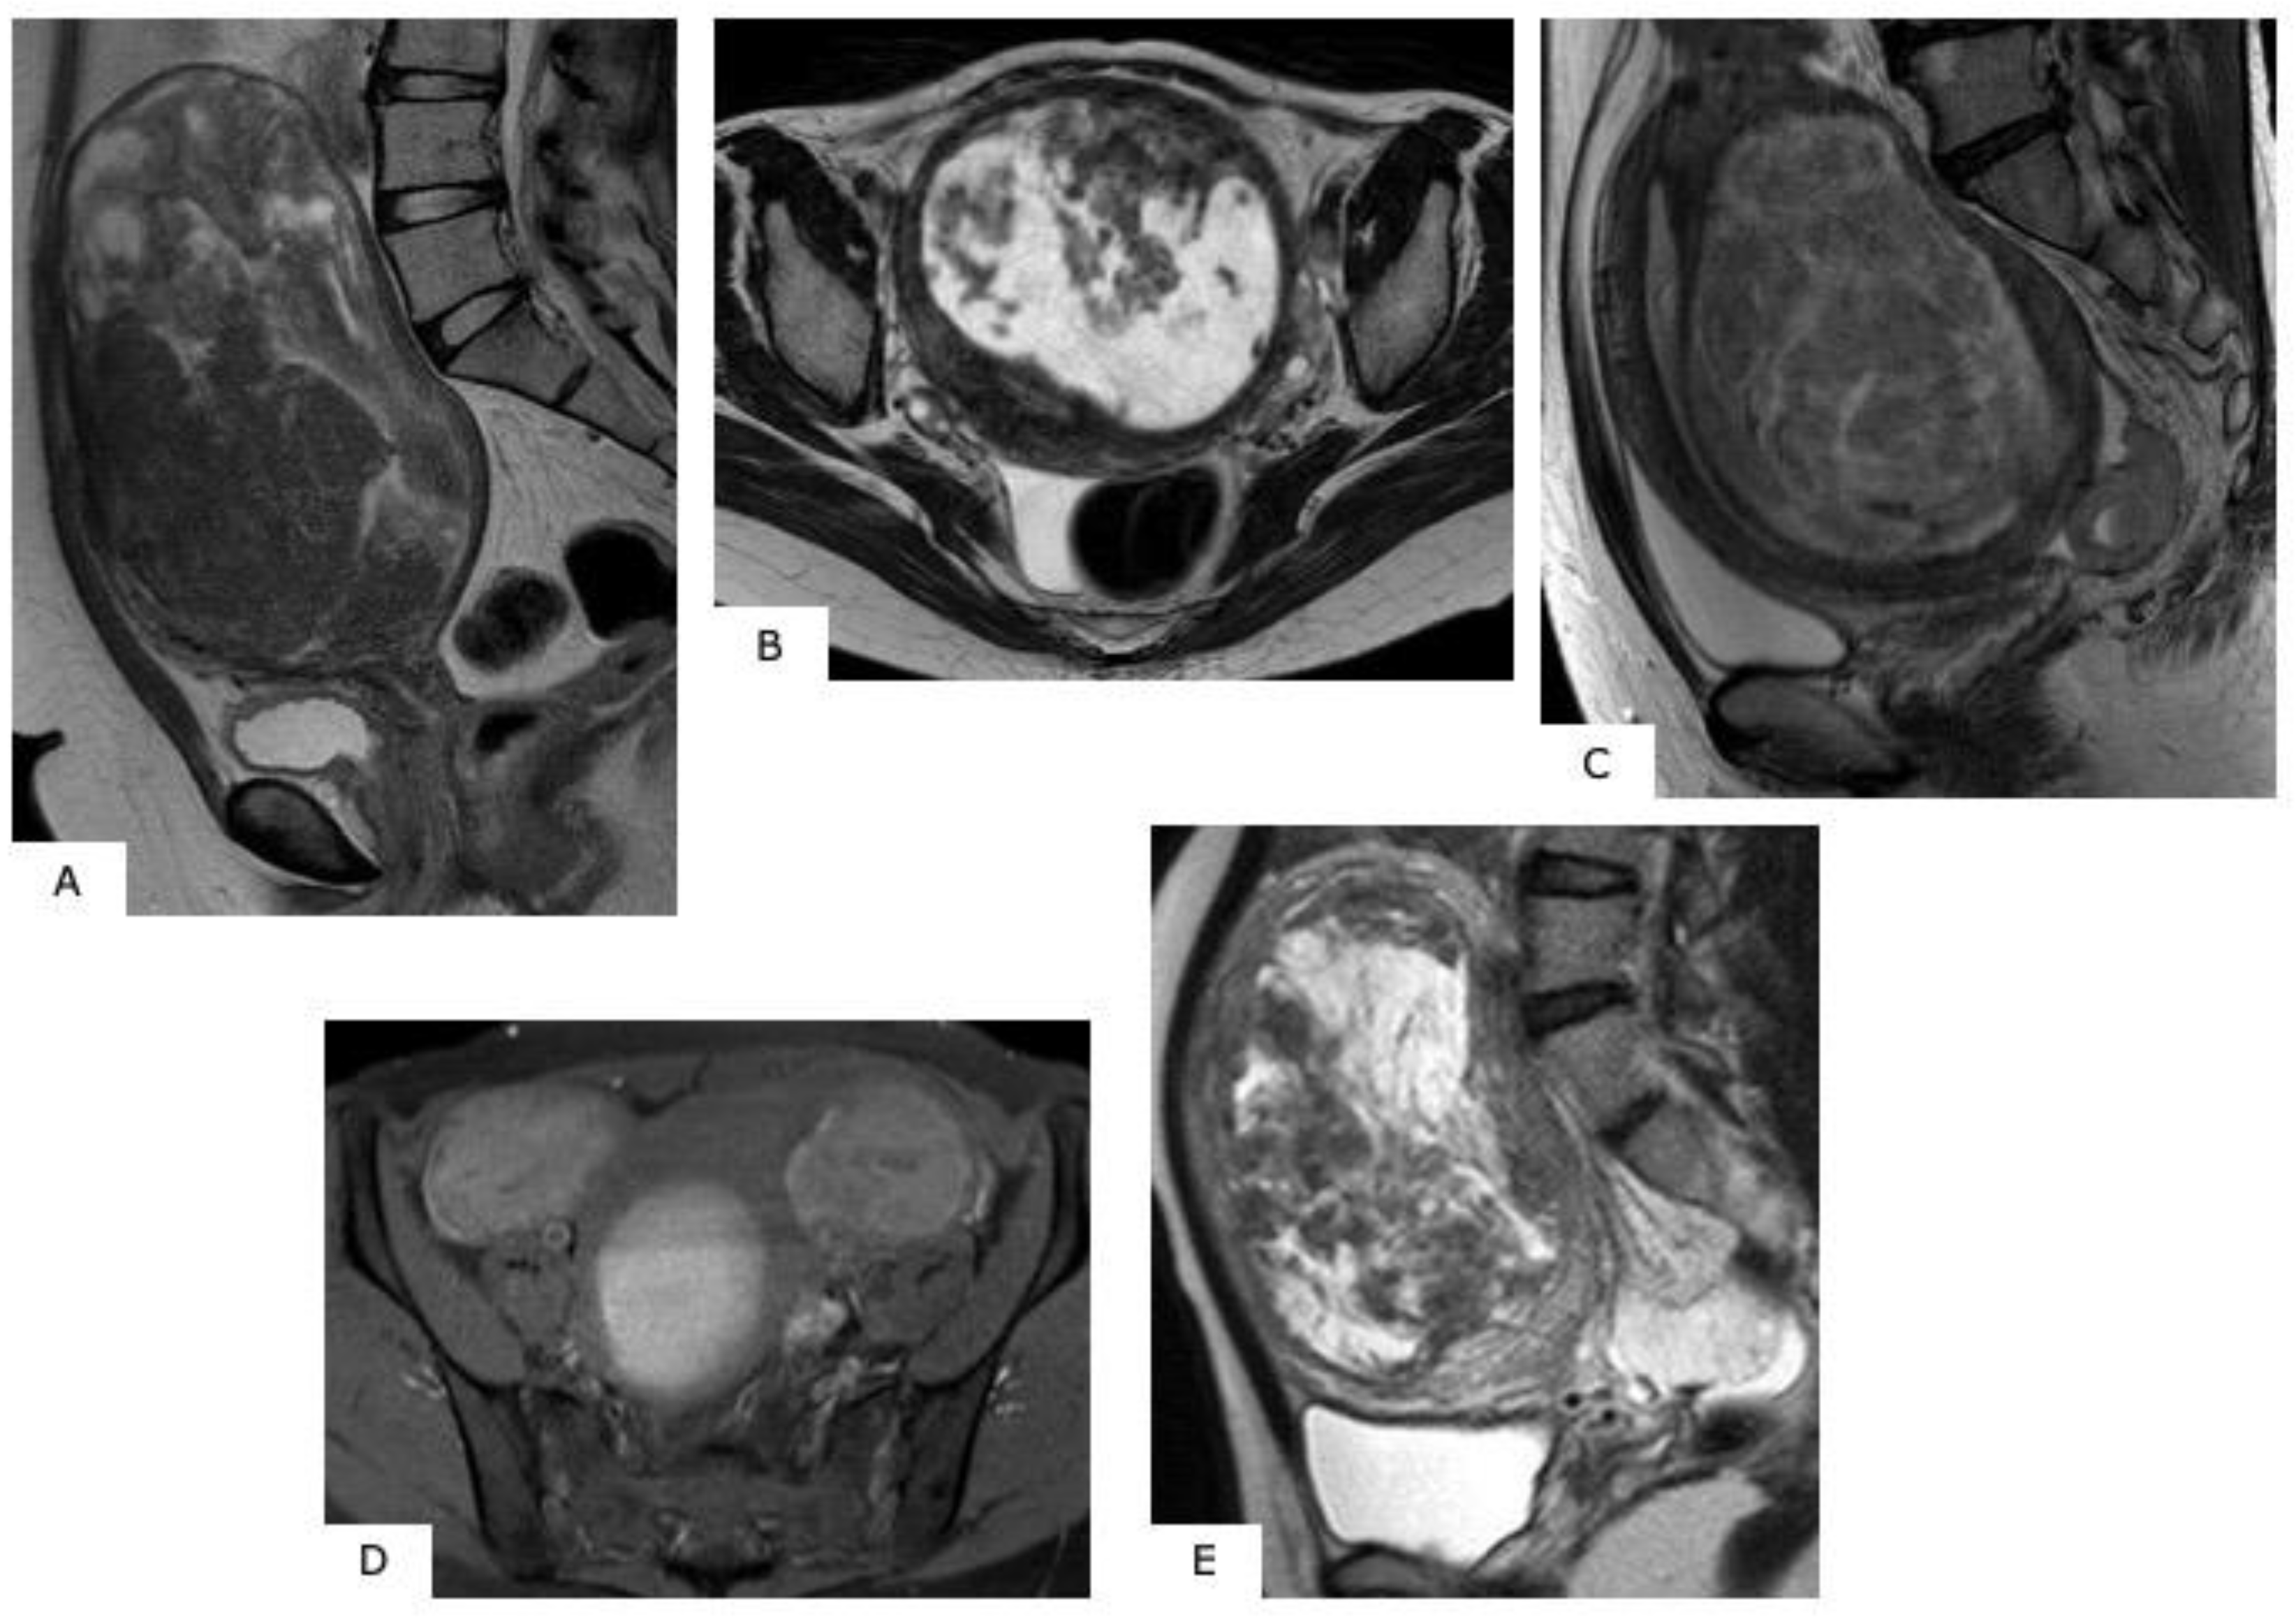

Figure 2.

MR images of degenerated leiomyoma. These images always require a differential diagnosis from sarcoma. (A): hyaline degeneration (T2WI), (B): leiomyoma with cystic change (T2WI), (C): cellular leiomyoma (T2WI), (D): red degeneration (T1WI), (E): myxoid degeneration (T2WI).